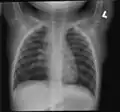

Medical imaging

Early in the disease chest radiography is typically normal but may show hyperinflation.[6] As the disease progresses a reticular pattern with thickening of airway walls may be present.[4][6] HRCT can also show air trapping when the person being scanned breathes out completely; it can also show thickening in the airway and haziness in the lungs.[11] A common finding on HRCT is patchy areas of decreased lung density, signifying reduced vascular caliber and air trapping.[6] This pattern is often described as a "mosaic pattern", and may indicate obliterative bronchiolitis.[6]

Chest radiograph demonstrates thickening and dilatation of the bronchioles